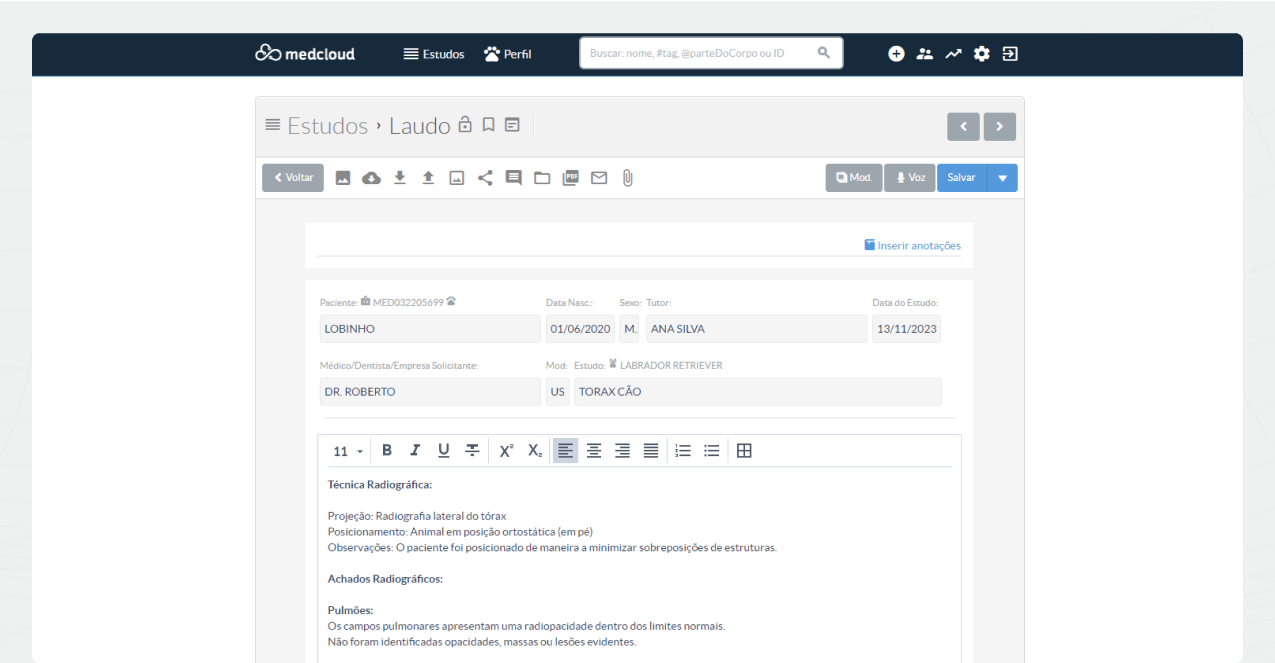

Cree informes mediante reconocimiento de voz, dictado digital y plantillas de informes estándar con solo unos pocos clics. Agregue imágenes y vídeos clave para informes multimedia.

Mejora tus informes, hazlos más fáciles de entender para los solicitantes y tutores con un editor de informes completo y accesible.

Reemplace las hojas de historial médico con un formulario digital. Crea tus cuestionarios de forma personalizada y vincúlalos a sus procedimientos adecuados. Al finalizar el cuestionario, el paciente podrá firmarlo digitalmente y el documento quedará guardado en su historial asistencial.

Con la firma electrónica ofrecemos comodidad y seguridad a sus pacientes, garantizando que tengan acceso a toda la información importante antes de realizar cualquier procedimiento.